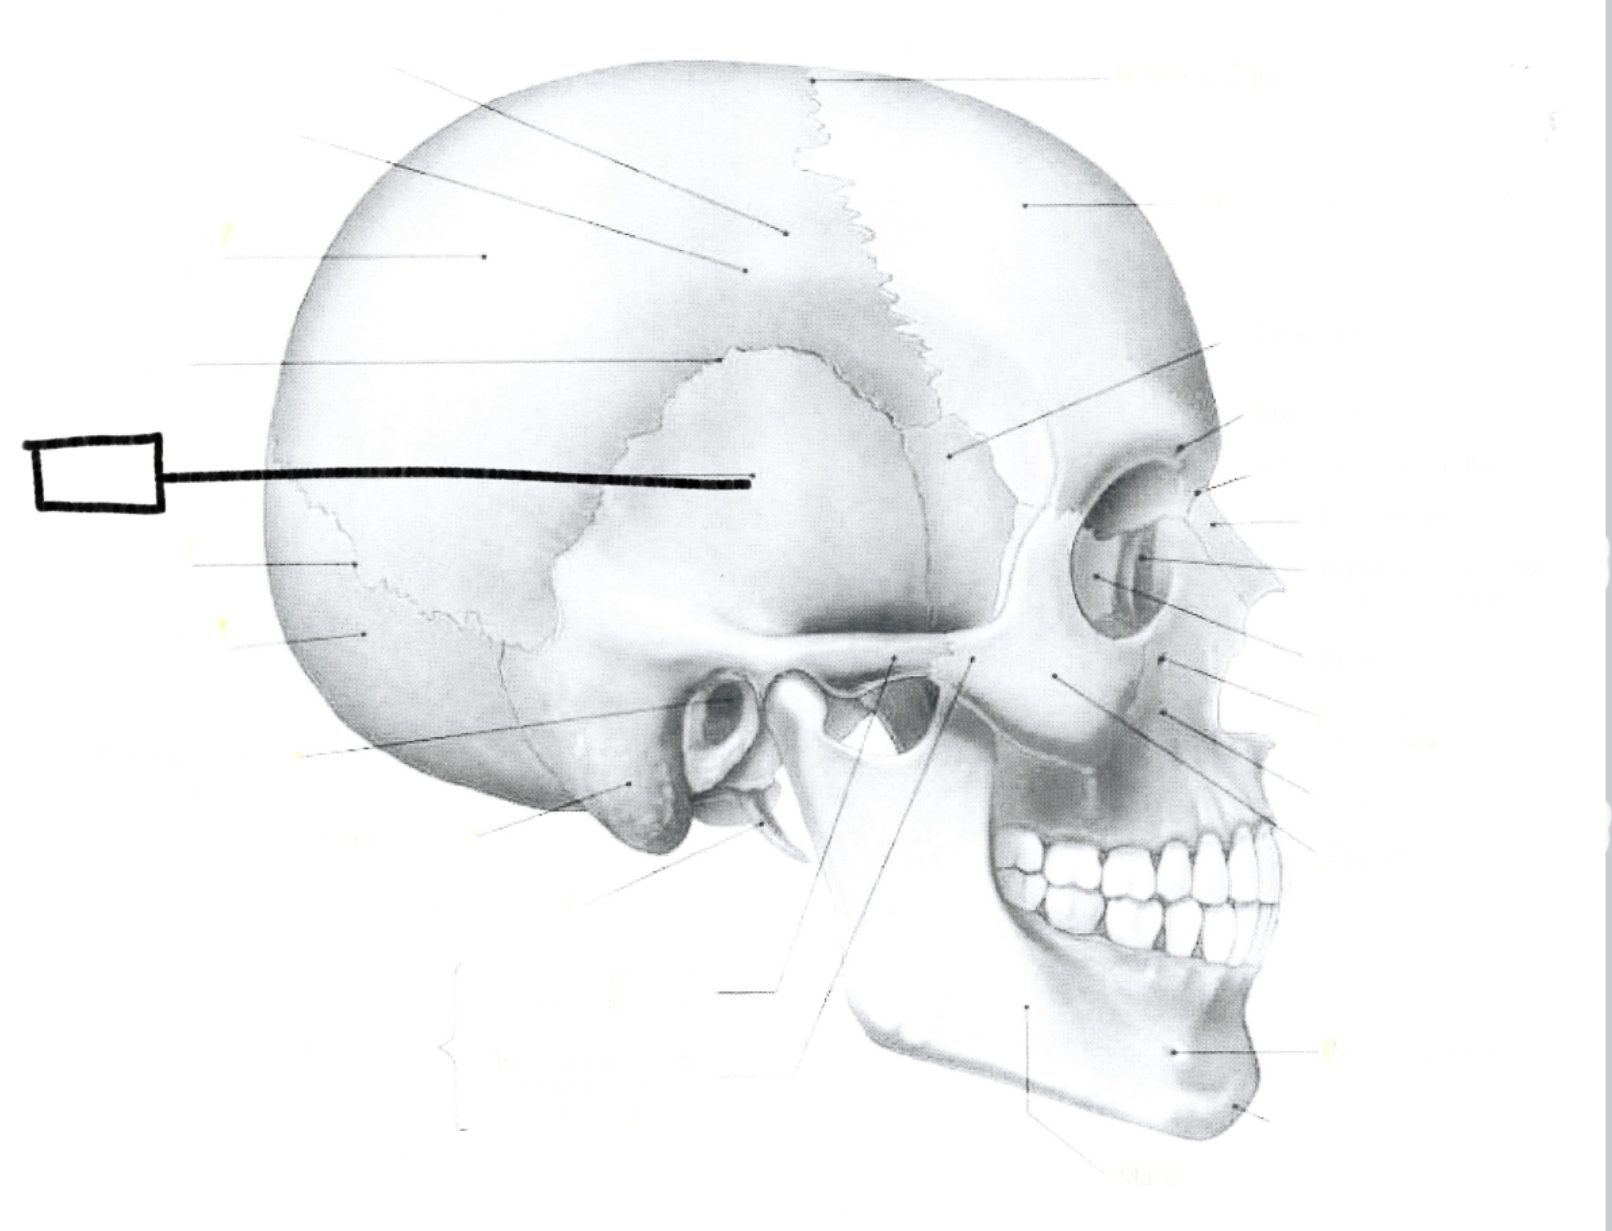

What is this?

Squamous suture